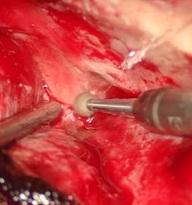

Extradural minipterional approach in clipping of ruptured and unruptured complex aneurysms in the “Luis N. Saenz” PNP Hospital Complex: case report

CRISTIAN SALAZAR C, ALLEN DIAZ I, RICARDO ROJAS D, MIGUEL GAITAN C, ARMANDO LUCAR F.